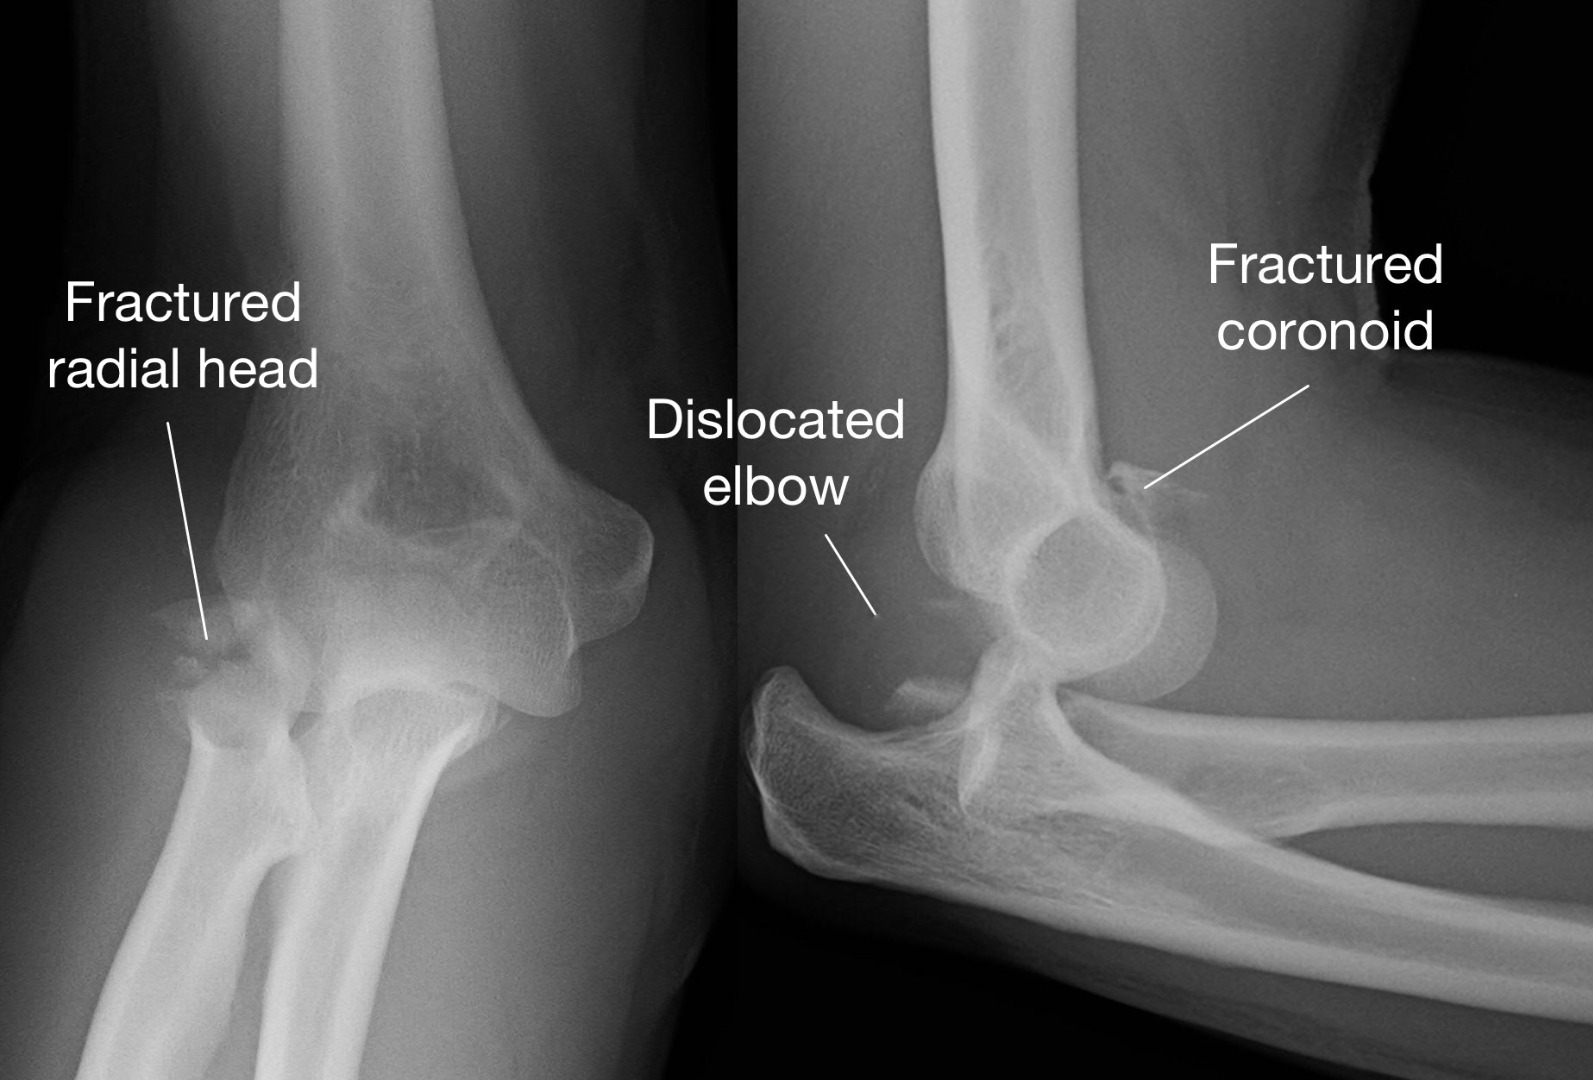

Understand the anatomy and function of the first metacarpal bone, a critical component of the human thumb. This guide covers its unique saddle joint structure, common fracture types, and clinical significance for hand mobility. Learn how this essential bone supports gripping and fine motor tasks, along with key recovery insights for injuries affecting the base of the thumb.